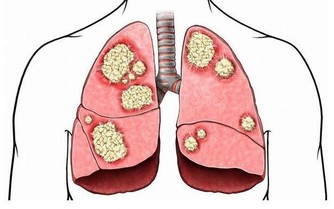

在我國自古就有“喜傷心”、“怒傷肝”、“思傷脾”、“憂傷肺”、“恐傷腎”的說法。

大量臨床醫學研究表明,小到感冒,大到冠心病和癌症,都與情緒有著密不可分的關係。

充滿心理矛盾、壓抑,經常感到不安全和不愉快的人,免疫力低下,經常感冒、一著急就喉嚨痛;緊張的人則會頭痛、血壓升高,容易引發心血管疾病;經常忍氣吞聲的人得癌症的機率是一般人的三倍。